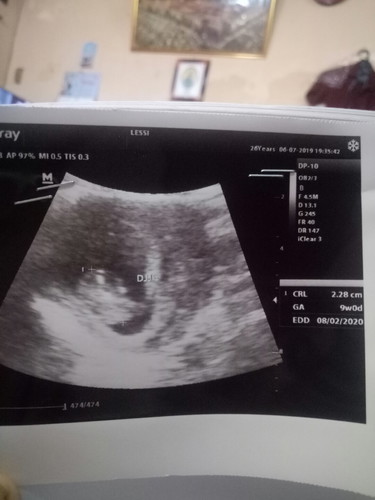

Bun, kmarin saya hari sabtu USG di tulis dokter kandungan saya umurnya 9 minggu pas. Tapi kalau dihitung dr HPHT saya umur kandungan saya harusnya 9 w 5 d. Apa dokter mengukur umur kandungan dr besar janinnya atau gimana ya bun???

Ini usg aku HPHT 8W 5d tapi dr hasil usg dokter karna ini twins yg kakak katanya udah 9w yg ade masih 8w 5d sesuai HPHT bundd...

HPHT itu belum pasti sesuai dengn umur kehamilan sebenarnya, karn adari nama nya aja HARI PERTAMA HAID kita yang TERAKHIR, kalo hari pertama haid kan berarti kita lagi haid, yaa sudah pasti kita blm di sebut hamil. karna perempuan di sebut hamil itu ketika sel telur berhasil di buahi oleh sperma. biasanya untuk perempuan yang pada umumnya haidnya cepet sekitar 4-5 hari bisa jadi hari pertama kehmailannya terjadi di hari ke 6, 7, atau 8 di hitung dri hari haid pertama. karna biasanya setelah dinding rahim sudah benar2 bersih indung telur biasanya akan langsung melepaskan sel telur, dan umur sel telur bertahan untuk segera di buahi itu 1-3 hari, tapi perhitungan ini juga kadang berbeda pada setiap perempuan. nahh klo setelah 3 hari sel telur tidak juga di buahi, atau bila dalam waktu 1-3 hari sel telur di lepaskan tapi kita tidak melakukan hubungan suami istri, maka sel telur akan bergerak lagi ke rahim dan menempel kerahim untuk persiapan haid di bulan selanjut nya. alias tidak terjadi kehamilan. tapi klo dalam 1-3 hari berhasil terjadi pembuahan oleh sperma, maka barulah terjadi yang namanya kehamilan, dan hari pertama kehamilan sebenarnya di hitung sejak sel telur berhasil di buahi sperma. adapun HPHT itu cuma agar mempermudah kita sebagai orang awam menghitung umur kehamilan kita. sekian. saya bukan bidan atau pun dokter, saya cuma mahasiswa biasa yang sangat suka membaca ibu2, dan hasil dari yang saya baca2 seputar proses kehamilan, menstruasi, dll itulah penjelasan yg bisa saya bagikan untuk ibu2 yang kungkin masih sering bingung karna hpht dan hasil usg menunjukkan umur kehamilan berbeda. begitu ibu2 hehehe